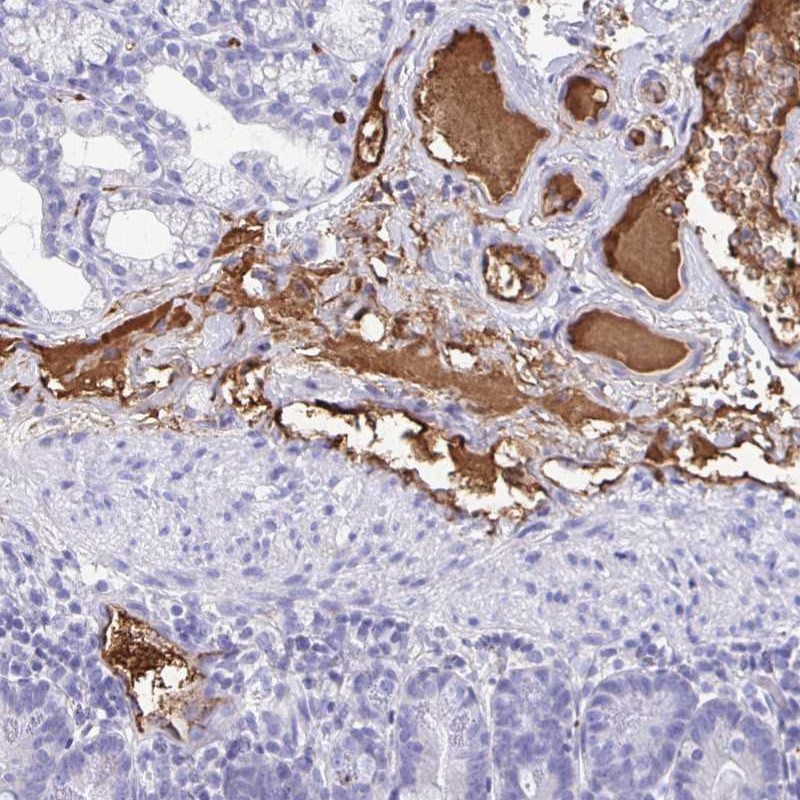

Immunohistochemical staining of human small intestine shows distinct positivity in plasma.